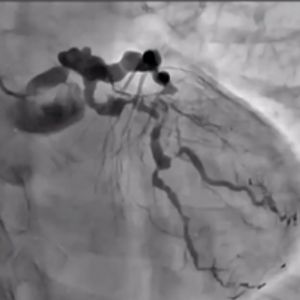

A new wave of technological innovation emerged in the late 2010s with the introduction of the 3D wiring technique. Developed by Dr. Atsunori Okamura of Sakurabashi Watanabe Hospital, this method enabled three-dimensional visualization of wires within occluded lesions, allowing precise manipulation by observing the movement of the wire tip in three dimensions. This rational approach transitioned CTO-PCI wiring from a skill dependent on tactile sensation to one guided by scientific observation.

The 3D wiring technique was further refined by expert operators across Japan, eventually establishing Tip Detection Antegrade Dissection Re-entry (TD-ADR) as a new standard in CTO-PCI. TD-ADR reignited global interest in CTO-PCI by providing a more systematic and reproducible methodology. More recently, HydroDynamic Contrast Recanalization (HDR) has emerged as a technique for performing antegrade CTO-PCI, leveraging the synergistic use of contrast microinjections and polymer-jacketed wires to further expand the technical options available for CTO-PCI.